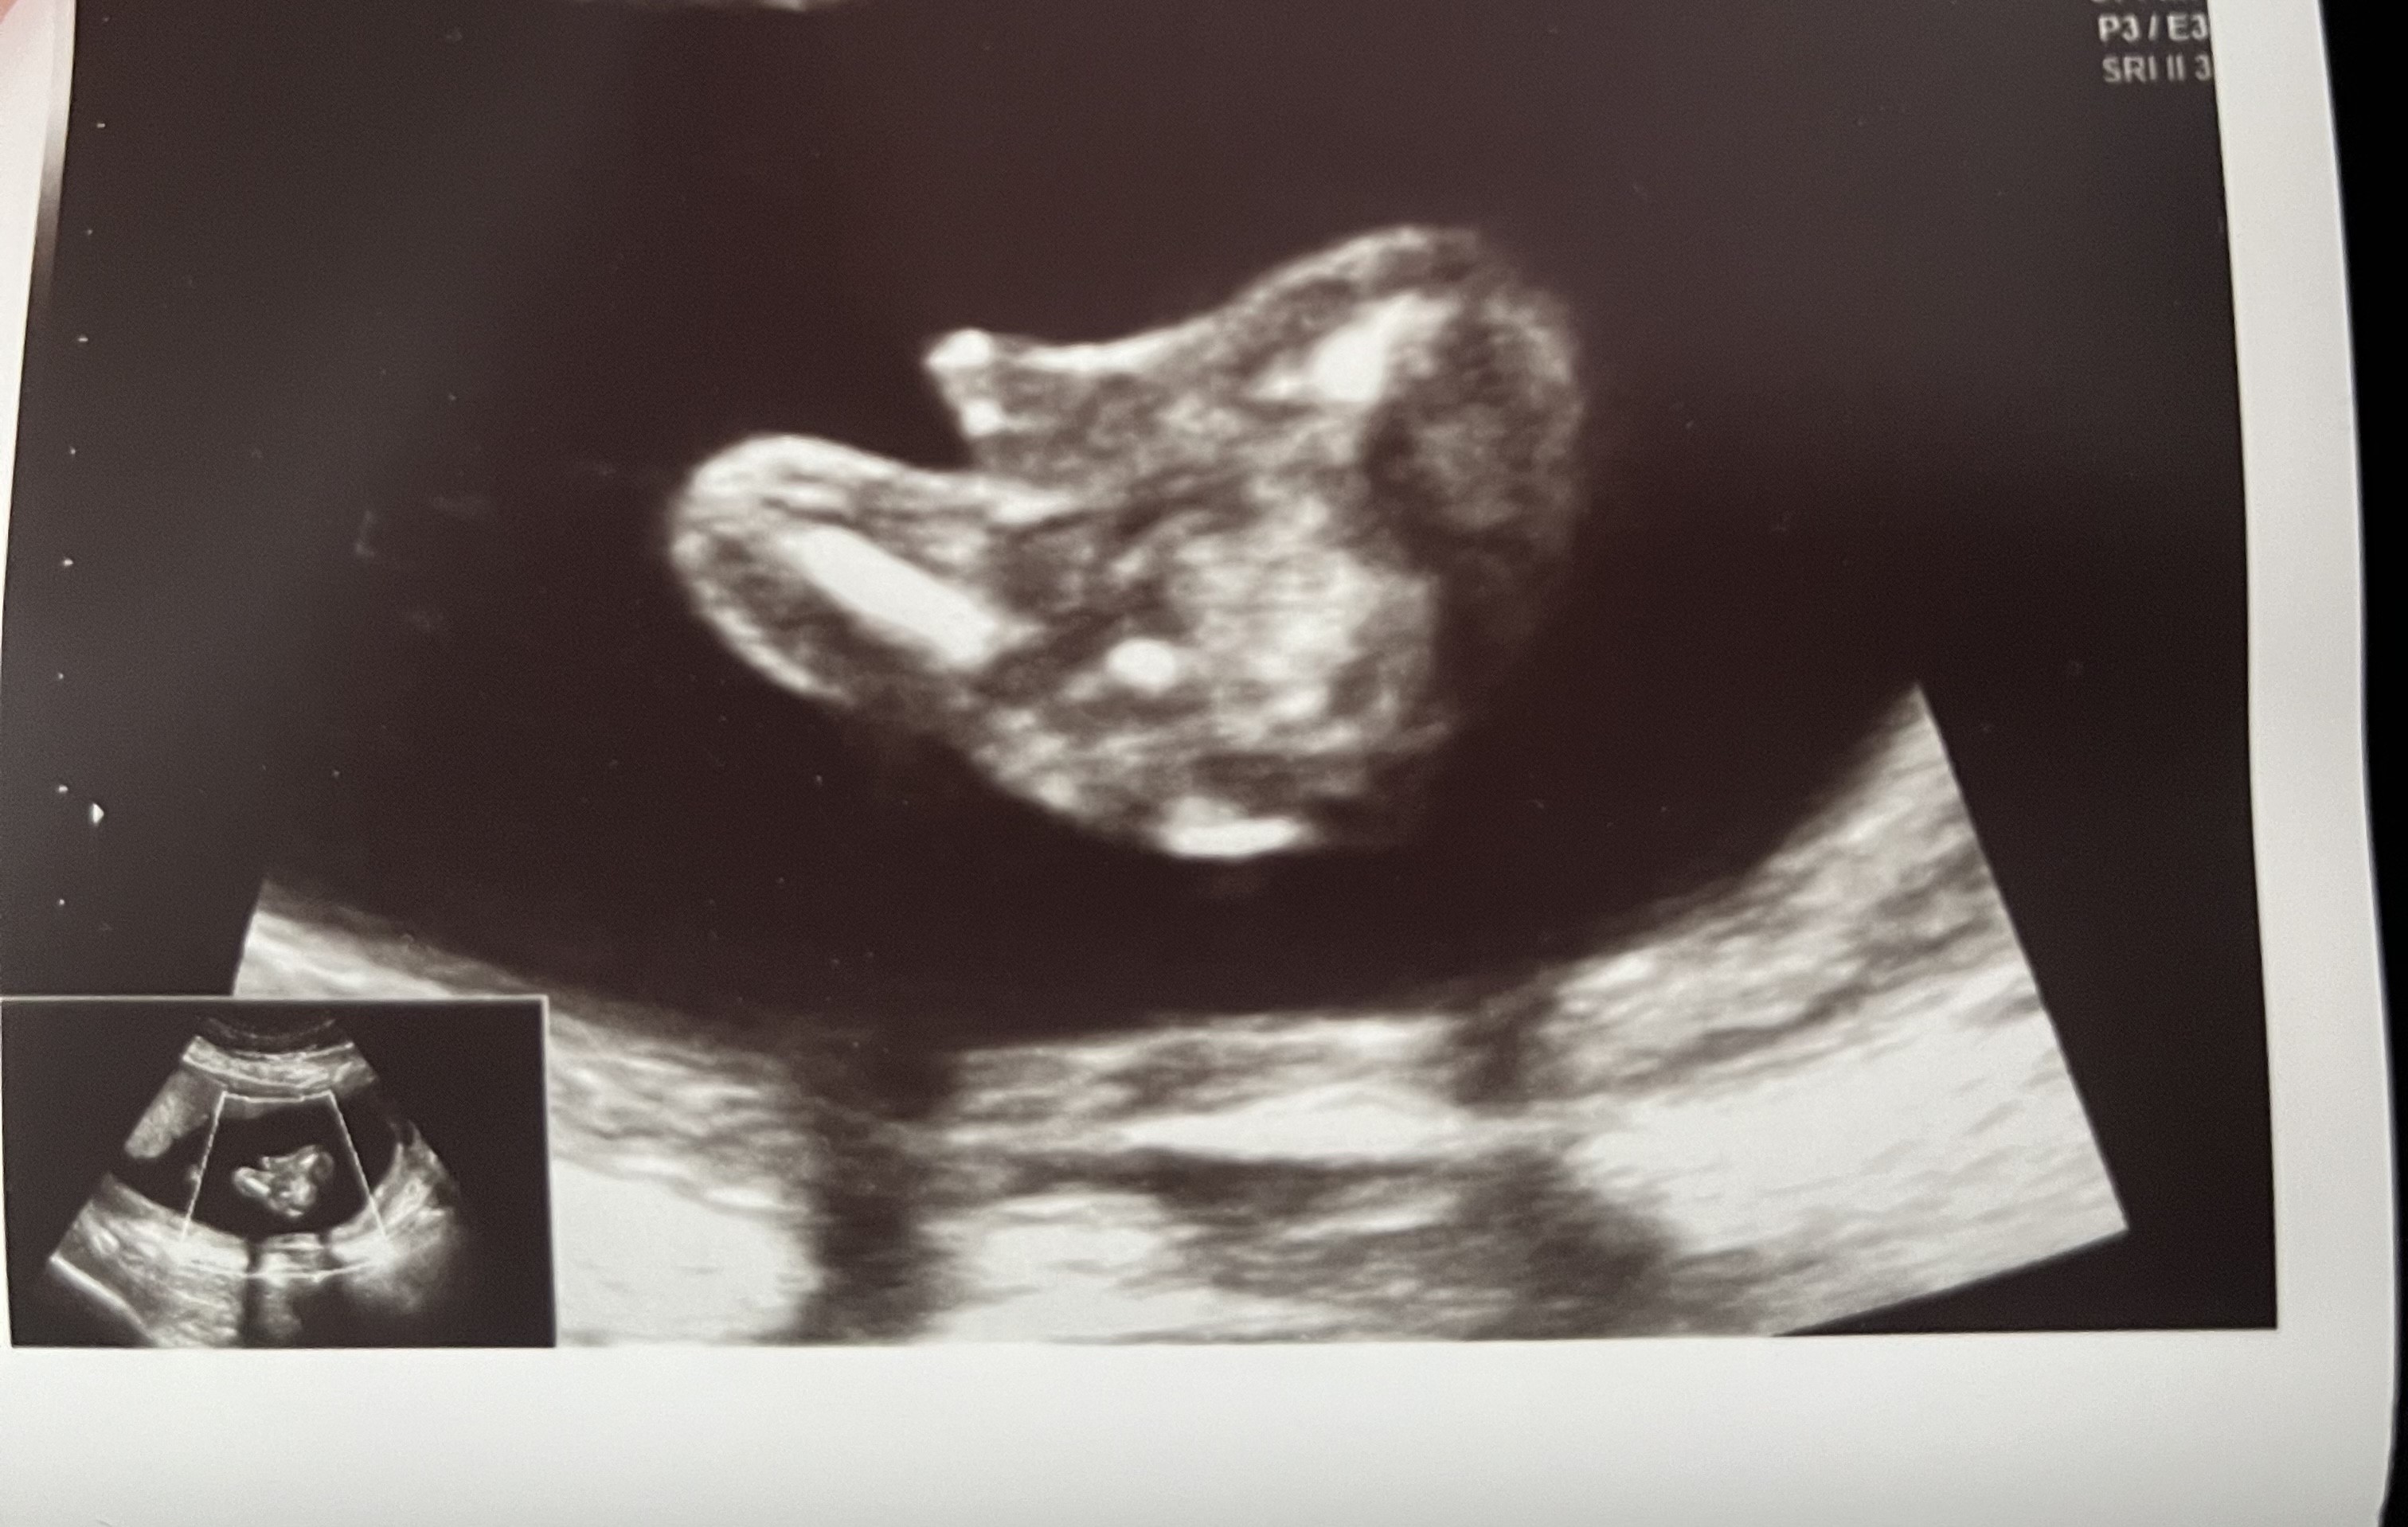

Cześć dziewczyny! Dzisiaj jestem po usg, nawet moja Pani Doktor zaczęła mieć wątpliwości i powiedziała, że to chyba jednak chlopczyk! :) ale numer.. co usg inna płeć 🙈

Hit :) a widziała mosznę? Na wcześniejszym zdjęciu było ewidentnie widać hamburgerka :)

Powiedziała tylko, że chlopczyk bo widzi jajeczka. Ja oczywiście nie widziałam nic jak to na każdym usg :) za tydzień mam 3 prenatalne mam nadzieję że wtedy lekarz bez wątpliwości powie co tam się kryje. Sama była zdziwiona, że tak wyszło tymbardziej że na poprzednim usg też dzieciątko było dobrze ułożone i nie widziała ani siusiaka ani jajeczek :)